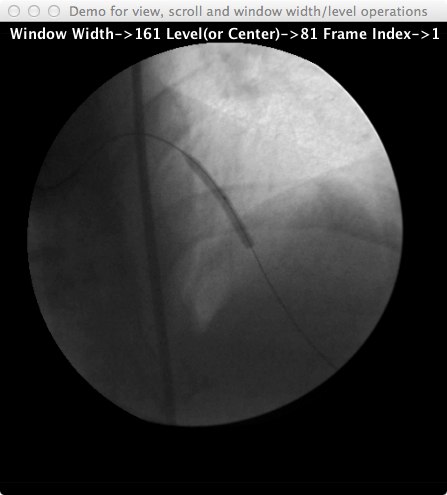

Now, click and drag the mouse on this window from left to right to control window width. Or, click and drag the mouse on this window from top to bottom for window level or centering. The screen capture below shows the code needed to achieve this behavior. As you can a lot of functionality is already provided by the SingleImagePanel class. The screen capture of the window showing the image as well as additional information regarding the image such as window width, level as well as the frame number are shown below the code illustration below as well.